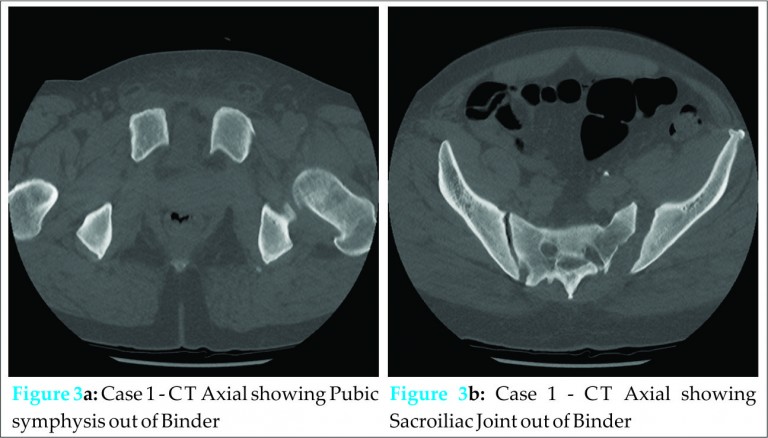

A pelvic radiograph was performed (Fig. 2) that showed diastasis of the pubic symphysis with an open sacroiliac joint on the left. His initial CT images were reviewed and a repeat pelvic CT was performed, which confirmed the radiographic findings (Figs. 3a and 3b).

His initial CT scan reported his injuries as bilateral lung contusions, a left L5 transverse fracture, left lower rib fractures, some soft tissue swelling on the anterior abdominal wall along the right lateral pelvis with no abdominal bleed, no pelvic bony injury (Figs. 1a, 1b and 1c) and no solid organ damage. Once his cervical spine was clinically and radiographically cleared, the pelvic binder was removed and he was sat up. He complained of lower back and left hip pain, which was attributed to the transverse process fracture and extensive bruising. However, following transfer to an orthopaedic ward his left hip pain continued despite analgesia with marked tenderness being found on left hip examination.